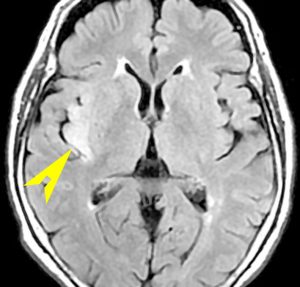

びまん性星細胞腫のIDH 野生型 wild type ゆっくり増大するものがあるか?

無症状で発見されたびまん性星細胞腫です。右側はその6年後,非常に緩徐に増大しています。良性のびまん性星細胞腫グレード2を疑い,手術で周囲脳も含めて完全摘出 supratotal resection しました。病理診断は,びまん性星細胞腫 WHO グレード2,MIB-1は2%,1p/19q欠失なしでした。大学病院の病理部ですが当時はIDHの検査をしていません。

術後4年目のものです。深部に小さな再発像が出現しました。これも予想の範囲内でした。これも手術で全摘出しました。普通ならあとは経過観察をするのみです。

しかし,病理診断では IDH1, IDH2ともに変異なし,野生型 wild typeでした。1p/19q non-codel, ATRX mutantです。急速な悪性化が懸念されましたので術後に局所放射線治療を加えました。それ以降は腫瘍再燃はありません。

経過は,IDH mutant diffuse astrocytoma WHO grade 2です。でも,再発像でwild typeでした。malignant transformationなのか?このような例をどう解釈してよいのか不明です。